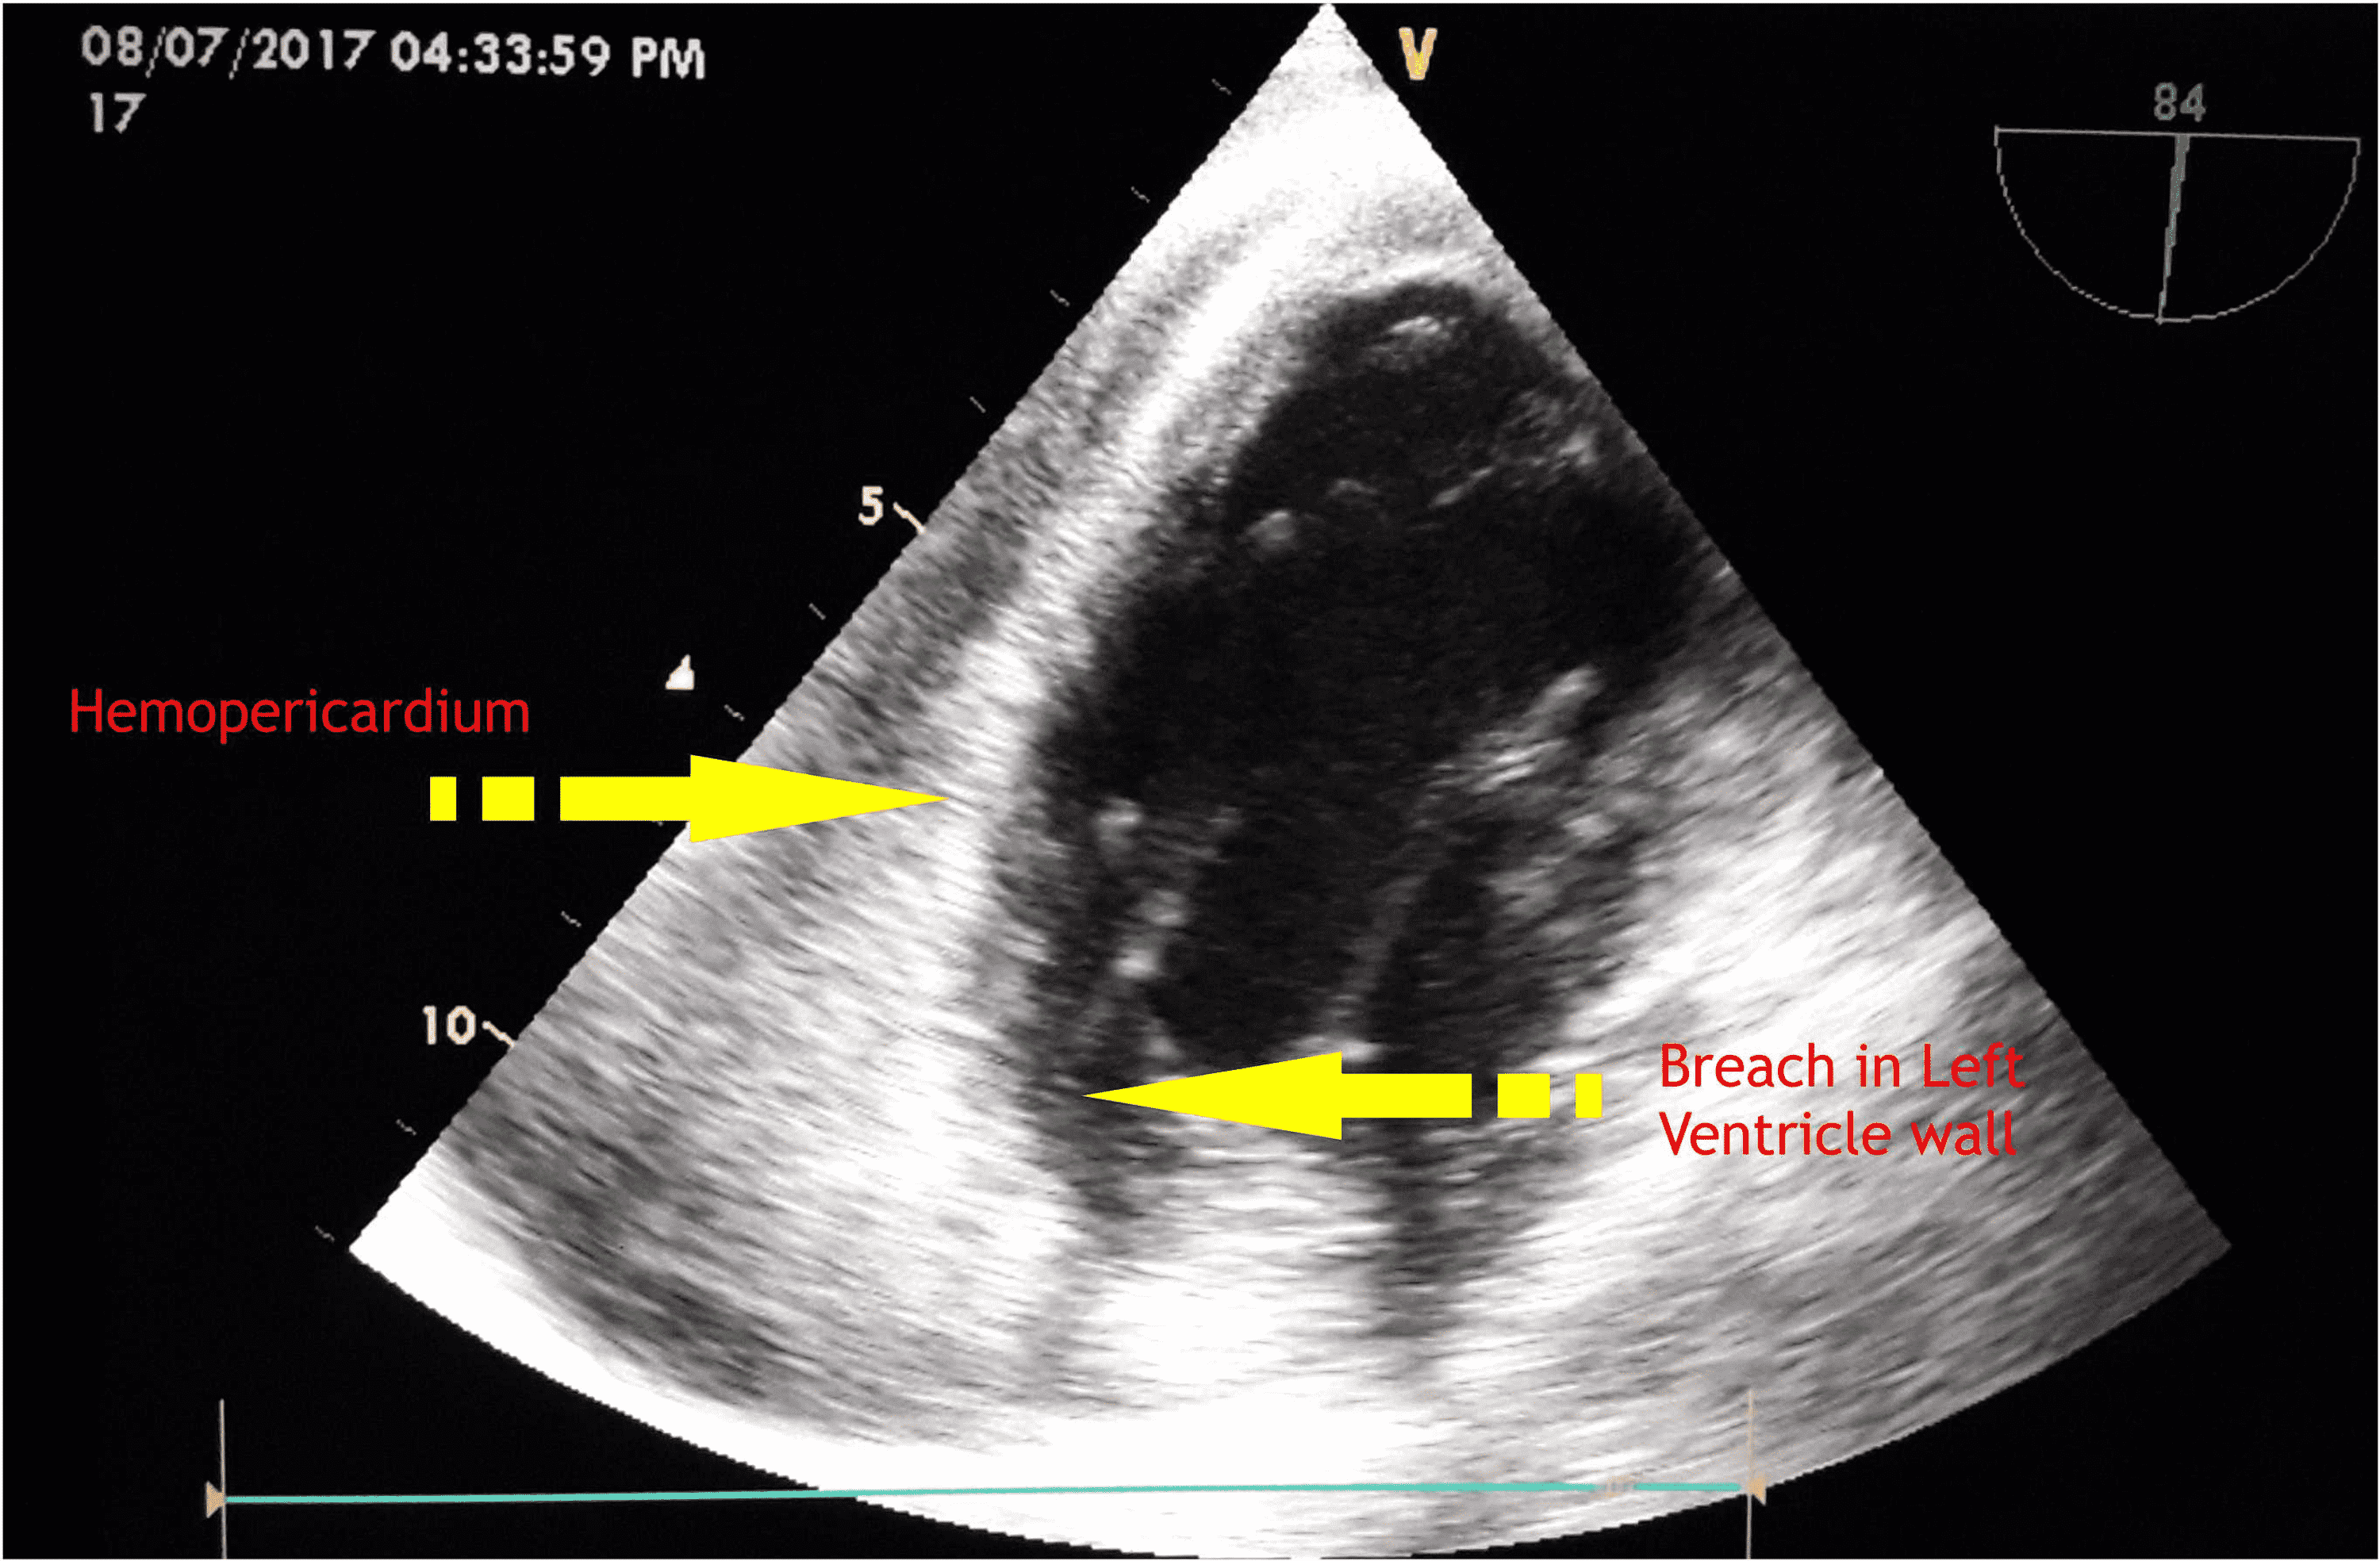

Case Report Free Wall Rupture . Without cardiac surgery, 94% of patients with left ventricular free wall rupture (lvfwr) due to tcm die. Pericardiocentesis revealed hemopericardium, and multidetector computed tomography angiography showed left ventricular free wall rupture. Here we present a case of a patient who suffered a left ventricular free wall rupture as a mechanical complication of myocardial. Through our case we highlight the. Left ventricular (lv) free wall ruptures (lvfwrs) of myocardial infarctions (mis) are still one of the most fatal mechanical complications. We are presenting the case of a 58 years old male with left ventricular free wall rupture occurred.

We are presenting the case of a 58 years old male with left ventricular free wall rupture occurred. Pericardiocentesis revealed hemopericardium, and multidetector computed tomography angiography showed left ventricular free wall rupture. Left ventricular (lv) free wall ruptures (lvfwrs) of myocardial infarctions (mis) are still one of the most fatal mechanical complications. Here we present a case of a patient who suffered a left ventricular free wall rupture as a mechanical complication of myocardial. Without cardiac surgery, 94% of patients with left ventricular free wall rupture (lvfwr) due to tcm die. Through our case we highlight the.

Case Report Free Wall Rupture Left ventricular (lv) free wall ruptures (lvfwrs) of myocardial infarctions (mis) are still one of the most fatal mechanical complications. We are presenting the case of a 58 years old male with left ventricular free wall rupture occurred. Here we present a case of a patient who suffered a left ventricular free wall rupture as a mechanical complication of myocardial. Without cardiac surgery, 94% of patients with left ventricular free wall rupture (lvfwr) due to tcm die. Through our case we highlight the. Left ventricular (lv) free wall ruptures (lvfwrs) of myocardial infarctions (mis) are still one of the most fatal mechanical complications. Pericardiocentesis revealed hemopericardium, and multidetector computed tomography angiography showed left ventricular free wall rupture.

Left ventricular free wall rupture after myocardial infarction a case report with rare live Case Report Free Wall Rupture Pericardiocentesis revealed hemopericardium, and multidetector computed tomography angiography showed left ventricular free wall rupture. Without cardiac surgery, 94% of patients with left ventricular free wall rupture (lvfwr) due to tcm die. Through our case we highlight the. We are presenting the case of a 58 years old male with left ventricular free wall rupture occurred. Left ventricular (lv) free wall. Case Report Free Wall Rupture.